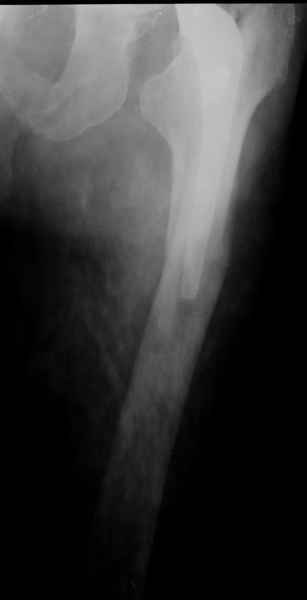

Произведено закрытое удлинение ножки эндопротеза с помощью ретроградного интрамедуллярного стержня. Продолжительность операции 3 часа. Два из них закрытое восстановление длины бедра диистрактором

таз-бедро.

новые снимки